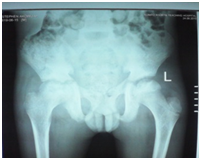

A 12-year-old boy was diagnosed with Sickle Cell Disease (SCD) with genotype SS about one year prior to. He presented with 2 months history of inability to walk and pain in both legs to Komfo Anokye Teaching Hospital in Kumasi, Ghana. The complaints were associated with marked weight loss and generalized body pain. He had been admitted about 2 weeks prior to the onset of current symptoms on account of abdominal pain and anaemia where he was haemo-transfused, given medications and subsequently discharged. There were no other significant findings in the past medical history, immunization history, nutritional and developmental histories. On examination he was found to be wasted (Weight for Height z-score <-3SD), pale, afebrile and anicteric. He had palpable axillary and inguinal lymph nodes (each measuring about 1cm to 1.5cm, mobile, non-tender and not matted). Vital signs were normal on admission. Other significant examination findings were obvious swelling of the right leg which was warm to touch, erythematous and tender on palpation. He had a gibbus deformity of the lower thoracic spine with no remarkable neurological findings in the lower limbs. A diagnosis of SCD with vaso-occlusive crises and cellulitis of the right leg was made with differential diagnosis of osteomyelitis, Deep Vein Thrombosis and Potts disease. Initial investigations revealed WBC of 13.51 X 109/dl with Neutrophils 8.83 (65.3%) Lymphocytes 4.27 (31.6%) and Monocytes 0.25(1.9%), Hemoglobin 7.1g/dl, MCV-70.7, MCH-22.4, Platelets: 538, ESR-117, INR-1.05, Prothrombin Time-14.3secs and blood sugar-6.5mmol/L. Malaria parasites were not seen on the blood smear and patient was negative for Retro-Viral Screen for HIV. Other investigations included Doppler Ultrasound, Chest X-ray, Pelvic x-ray, Thoraco-lumbo-sacral spine X-ray (Figure 1-10). Blood culture and sensitivity could not be done at the time of admission as microbiology service in the hospital had a brief logistic challenge. Radiological findings revealed the following: Reduction in the vertebral body heights of T7-T10 with associated reduction in the intervertebral disc spaces and crowding of the posterior ribs. A paravertebral soft tissue mass extending from T4 vertebral level to T11. Coarse trabeculation and sclerosis of the ribs noted. Expansion of the anterior end of the left 8th rib with ill-defined lytic areas. Buckling of the cortex of the lateral aspect of the left 9th rib, suggestive of a fracture. The imaged portion of the proximal humerus shows periarticular osteopenia. Also noted was relatively small left humeral head with left glenohumeral joint space. There are patchy homogenous opacities in both lung fields predominantly in the lower zones. There was associated silhouetting of the hemi diaphragms bilaterally and the cardiac shadow. There was generalized sclerosis of the imaged pelvic bones with coarsening of the trabeculae. The right femoral head was deformed and expanded with sclerosis and lytic areas within. There was associated narrowing of the right hip joint space. The left femoral head also showed patchy lucencies. No deformity of the left femoral head seen. The left hip joint space appeared normal. Also noted was fusion of the sacroiliac joints bilaterally. There was diffuse sclerosis of the imaged vertebrae with coarse trabeculae. The vertebral endplates of L1/L2 and L3/L4 showed sharp depression at the margins with a flat base centrally giving it the H shaped appearance. Also noted were ill-defined lytic areas in the L3 to L5 vertebrae with associated end plate irregularities and reduced intervertebral disc spaces at L3/L4 and L4/L5. No paravertebral soft tissue mass seen. No fracture or listhesis seen. Changes of the thoracic spine were described under the chest x-ray.

Figure 2 Pelvic X-ray of patient.

Figure 3 Pelvic X-ray of patient.

These radiological diagnostic features were suggestive of sickle cell disease with Thoracolumbar spondylodiscitis, likely pyogenic; Bilateral Avascular Necrosis of the femoral head (early on the left); Septic arthritis of the right hip and left shoulder joint; Osteomyelitis of the left 8th and 9th ribs. Doppler Ultrasound of the lower limb revealed the following: The right common femoral and superficial femoral veins were of normal lumen with good wall to wall compressibility, good colour doppler and spectral wave form properties. The right popliteal and posterior tibial veins however showed extensive echogenic intraluminal-filling defect with resultant loss of wall-to-wall compressibility (percentage stenosis 76%). The accompanying arteries were of normal size and caliber and showed good colour doppler and spectral properties. There was thickening of the subcutaneous tissue with dilated fluid channels seen in the right foot. Inguinal as well as popliteal lymph nodes with retention of their fatty hilum noted averaging 0.9*0.5cm. Also noted was a 1.4*0.9*1.5cm (volume about 1.0ml) anechoic collection with low-level internal echoes at the medial aspect of the proximal thigh muscles; suggestive of inflammatory changes. Based on the Doppler findings a clinical diagnosis of Right Popliteal and Posterior Tibial Vein Thrombosis with Pyomyositis in a Sickle Cell Disease patient was considered and patient was subsequently administered subcutaneous Enoxaparin 40mg daily as well as Warfarin 3mg nocte, IV Clindamycin 150mg qid, IV Ciprofloxacin. After 2 days of Warfarin and Enoxaparin, INR and PT were repeated and results were 1.1 and 15.1s respectively. The child was followed up closely for four weeks and subsequently discharge. A repeat Doppler finding revealed a completely resolved thrombus with no evidence of DVT.